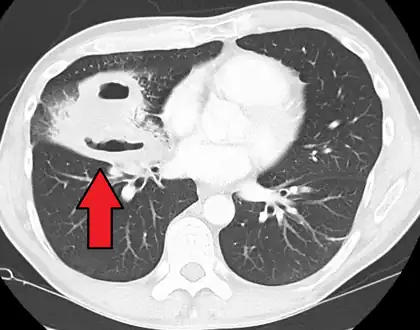

| CT scan showing bilateral pneumonia with abscesses and effusions. | |

Pulmonary abscess on CT scan

Pulmonary abscess on CT scan -